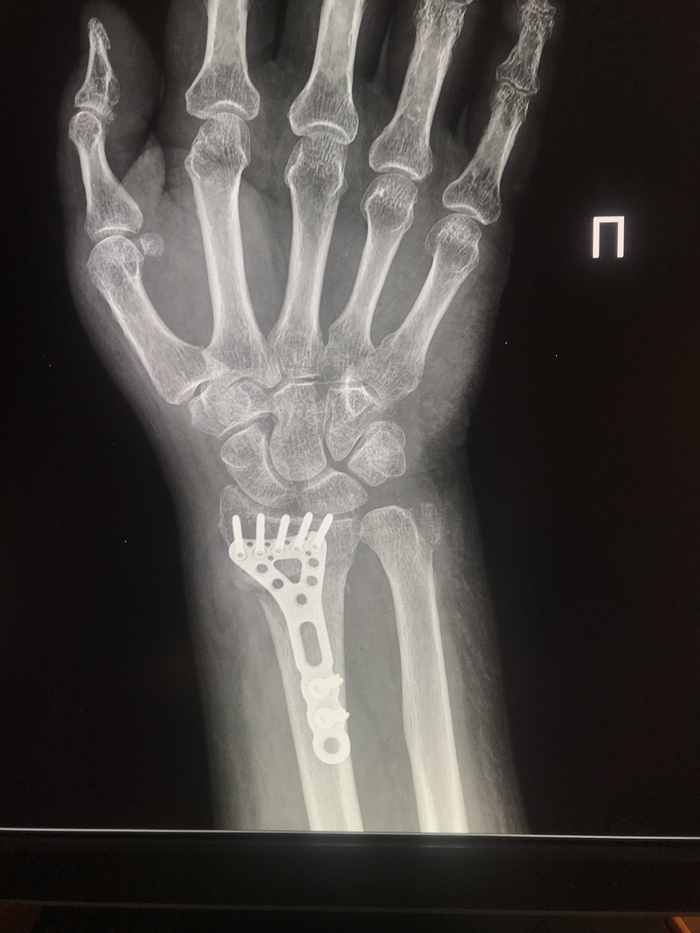

Другой пациент, тоже электросамокат, падение и результат.